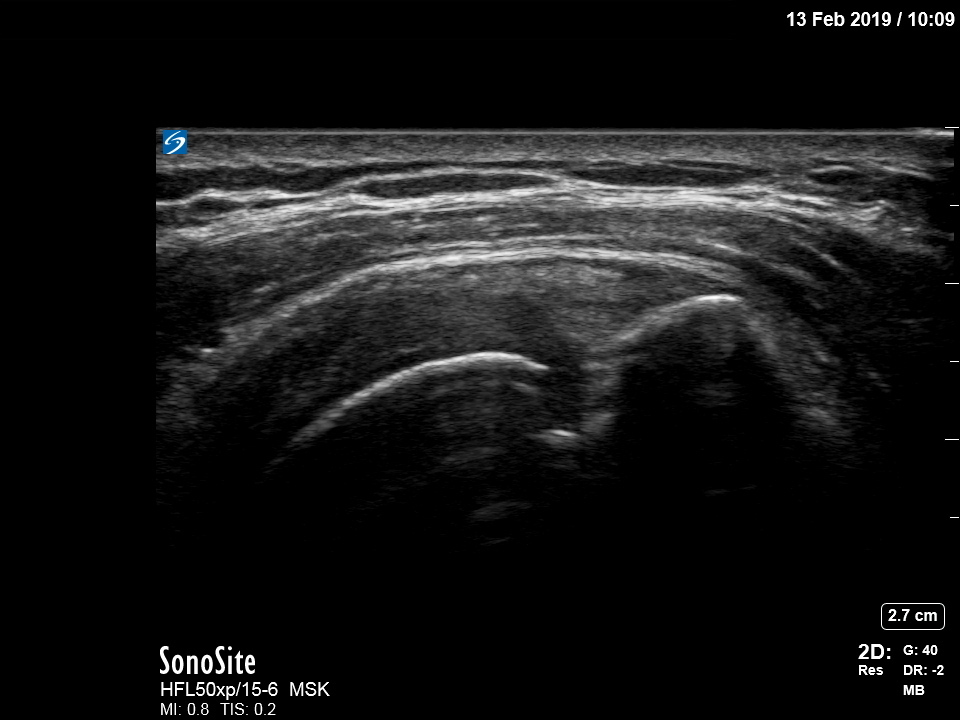

肩回旋腱板断裂の画像